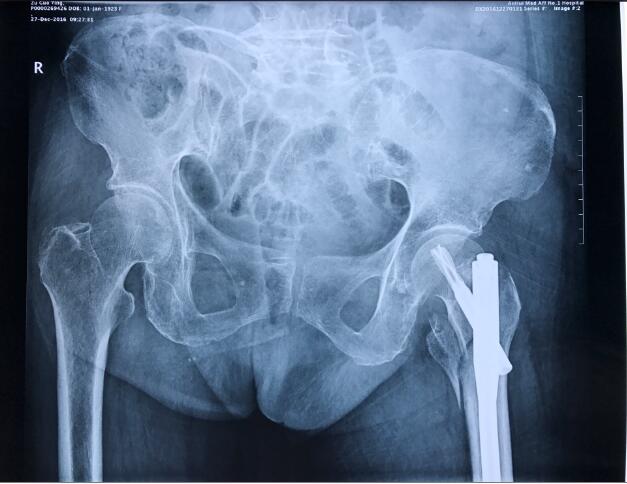

祖奶奶93岁高龄,因不慎摔伤致左侧股骨粗隆间骨折,伤后前往附近医院就诊。因患者高龄,合并糖尿病,手术风险极高,该院放弃治疗,转入我院关节与显微修复外科就诊,我科胡孔足主任术前结合患者综合情况,联合内科、麻醉科会诊,控制糖尿病,结合神经阻滞麻醉,采用股骨近端防旋髓内钉(PFNA)闭合复位内固定方案,以最小的创伤获得良好的固定。手术顺利,术后患者恢复良好。术后两天即可扶拐下地行走,迅速恢复生活自理能力。老年股骨粗隆间骨折由于内固定手术要求高,失败率较高,很多医院建议放弃内固定术,采用人关节置换术。但是人工关节置换术存在手术损伤大,术后容易脱位等问题,患者恢复仍然困难。相对于人工关节置换手术,闭合复位髓内内固定具有创伤小,出血少,对髋部肌群未造成明显干扰的特点,降低了感染风险,避免了人工关节脱位、人工关节翻修等棘手问题,经过康复训练后可以很好恢复功能。